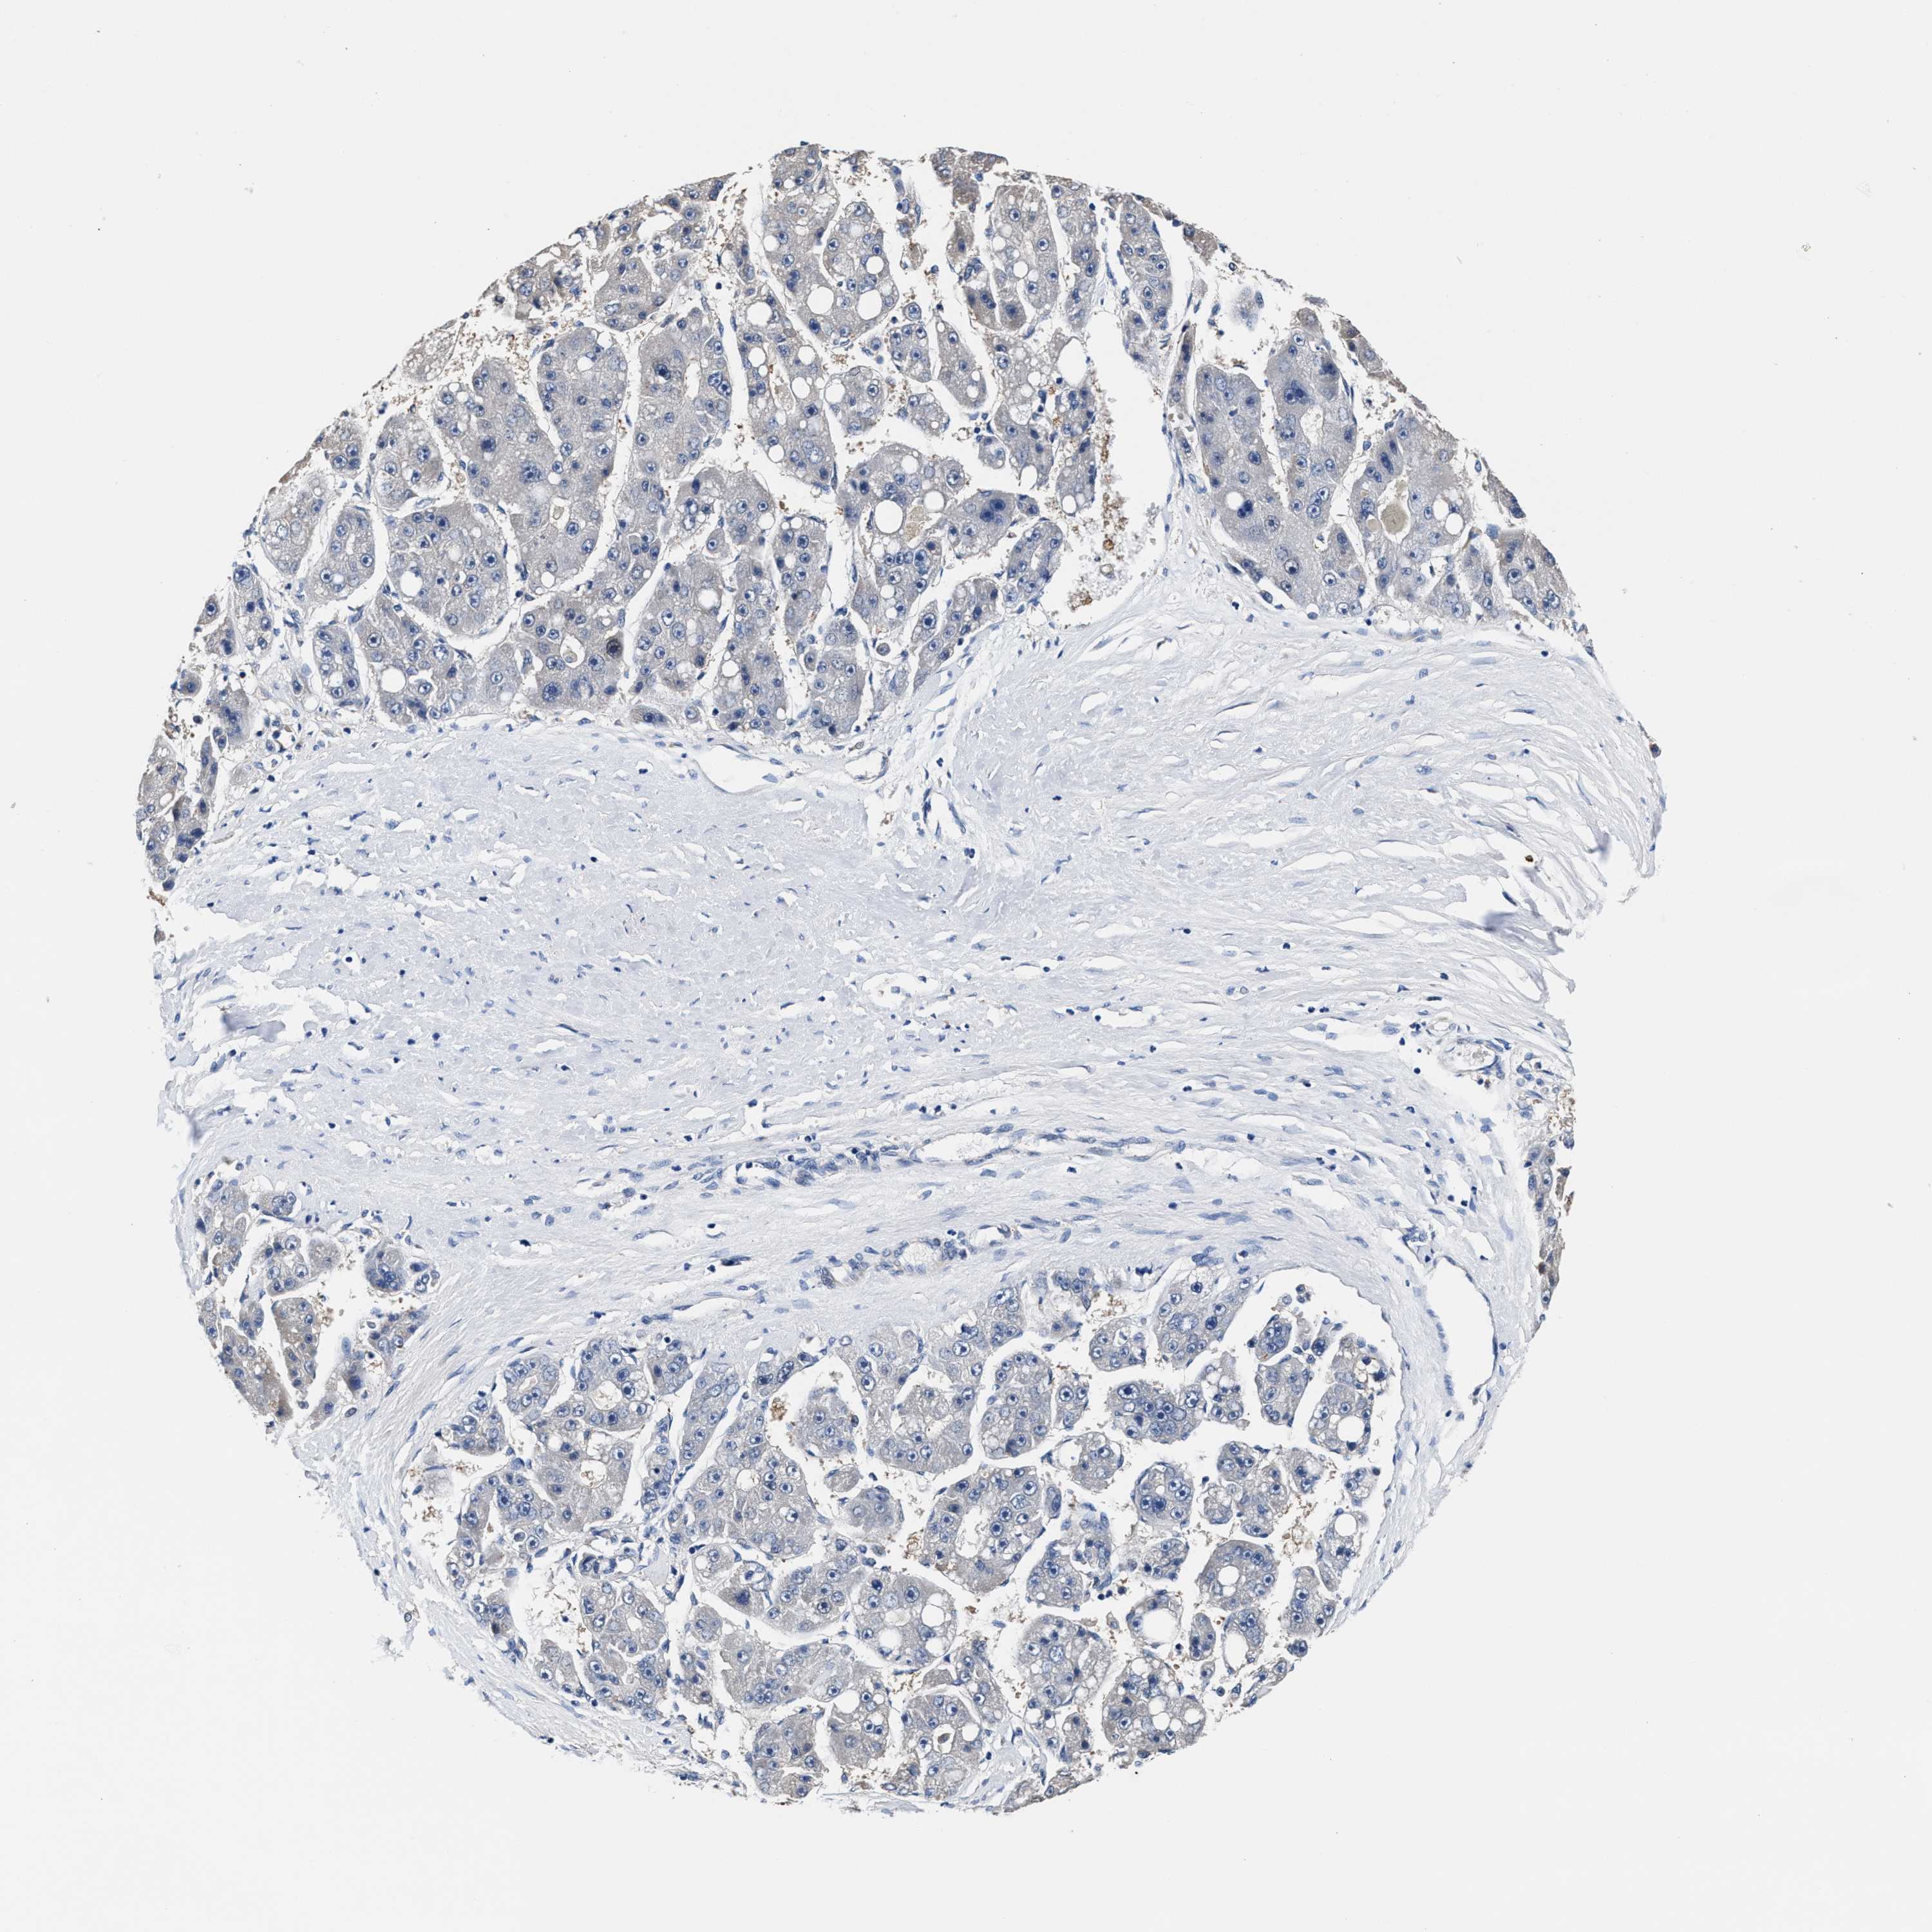

LIVER CANCER - Protein expressioni

A mouse-over function shows sample information and annotation data. Click on an image to view it in a full screen mode. Samples can be filtered based on level of antibody staining by selecting one or several of the following categories: high, medium, low and not detected. The assay and annotation is described here.

Note that samples used for immunohistochemistry by the Human Protein Atlas do not correspond to samples in the TCGA dataset.

Antibody stainingi

Antibody staining in the annotated cell types in the current human tissue is reported as not detected, low, medium, or high, based on conventional immunohistochemistry profiling in selected tissues. This score is based on the combination of the staining intensity and fraction of stained cells.

Each image is clickable and will lead to virtual microscopy that enables deeper exploration of all samples and also displays staining intensity scores, fraction scores and subcellular localization as well as patient and tissue information for each sample.

HPA048652

HPA055972

HPA055973

CAB022669

CAB047357

Staining

High

Medium

Low

Not detected

Intensity

Strong

Moderate

Weak

Negative

Quantity

>75%

75%-25%

<25%

None

Location

Nuclear

Cytoplasmic/membranous

Cytoplasmic/membranous,nuclear

Cholangiocarcinoma

Carcinoma, Hepatocellular, NOS